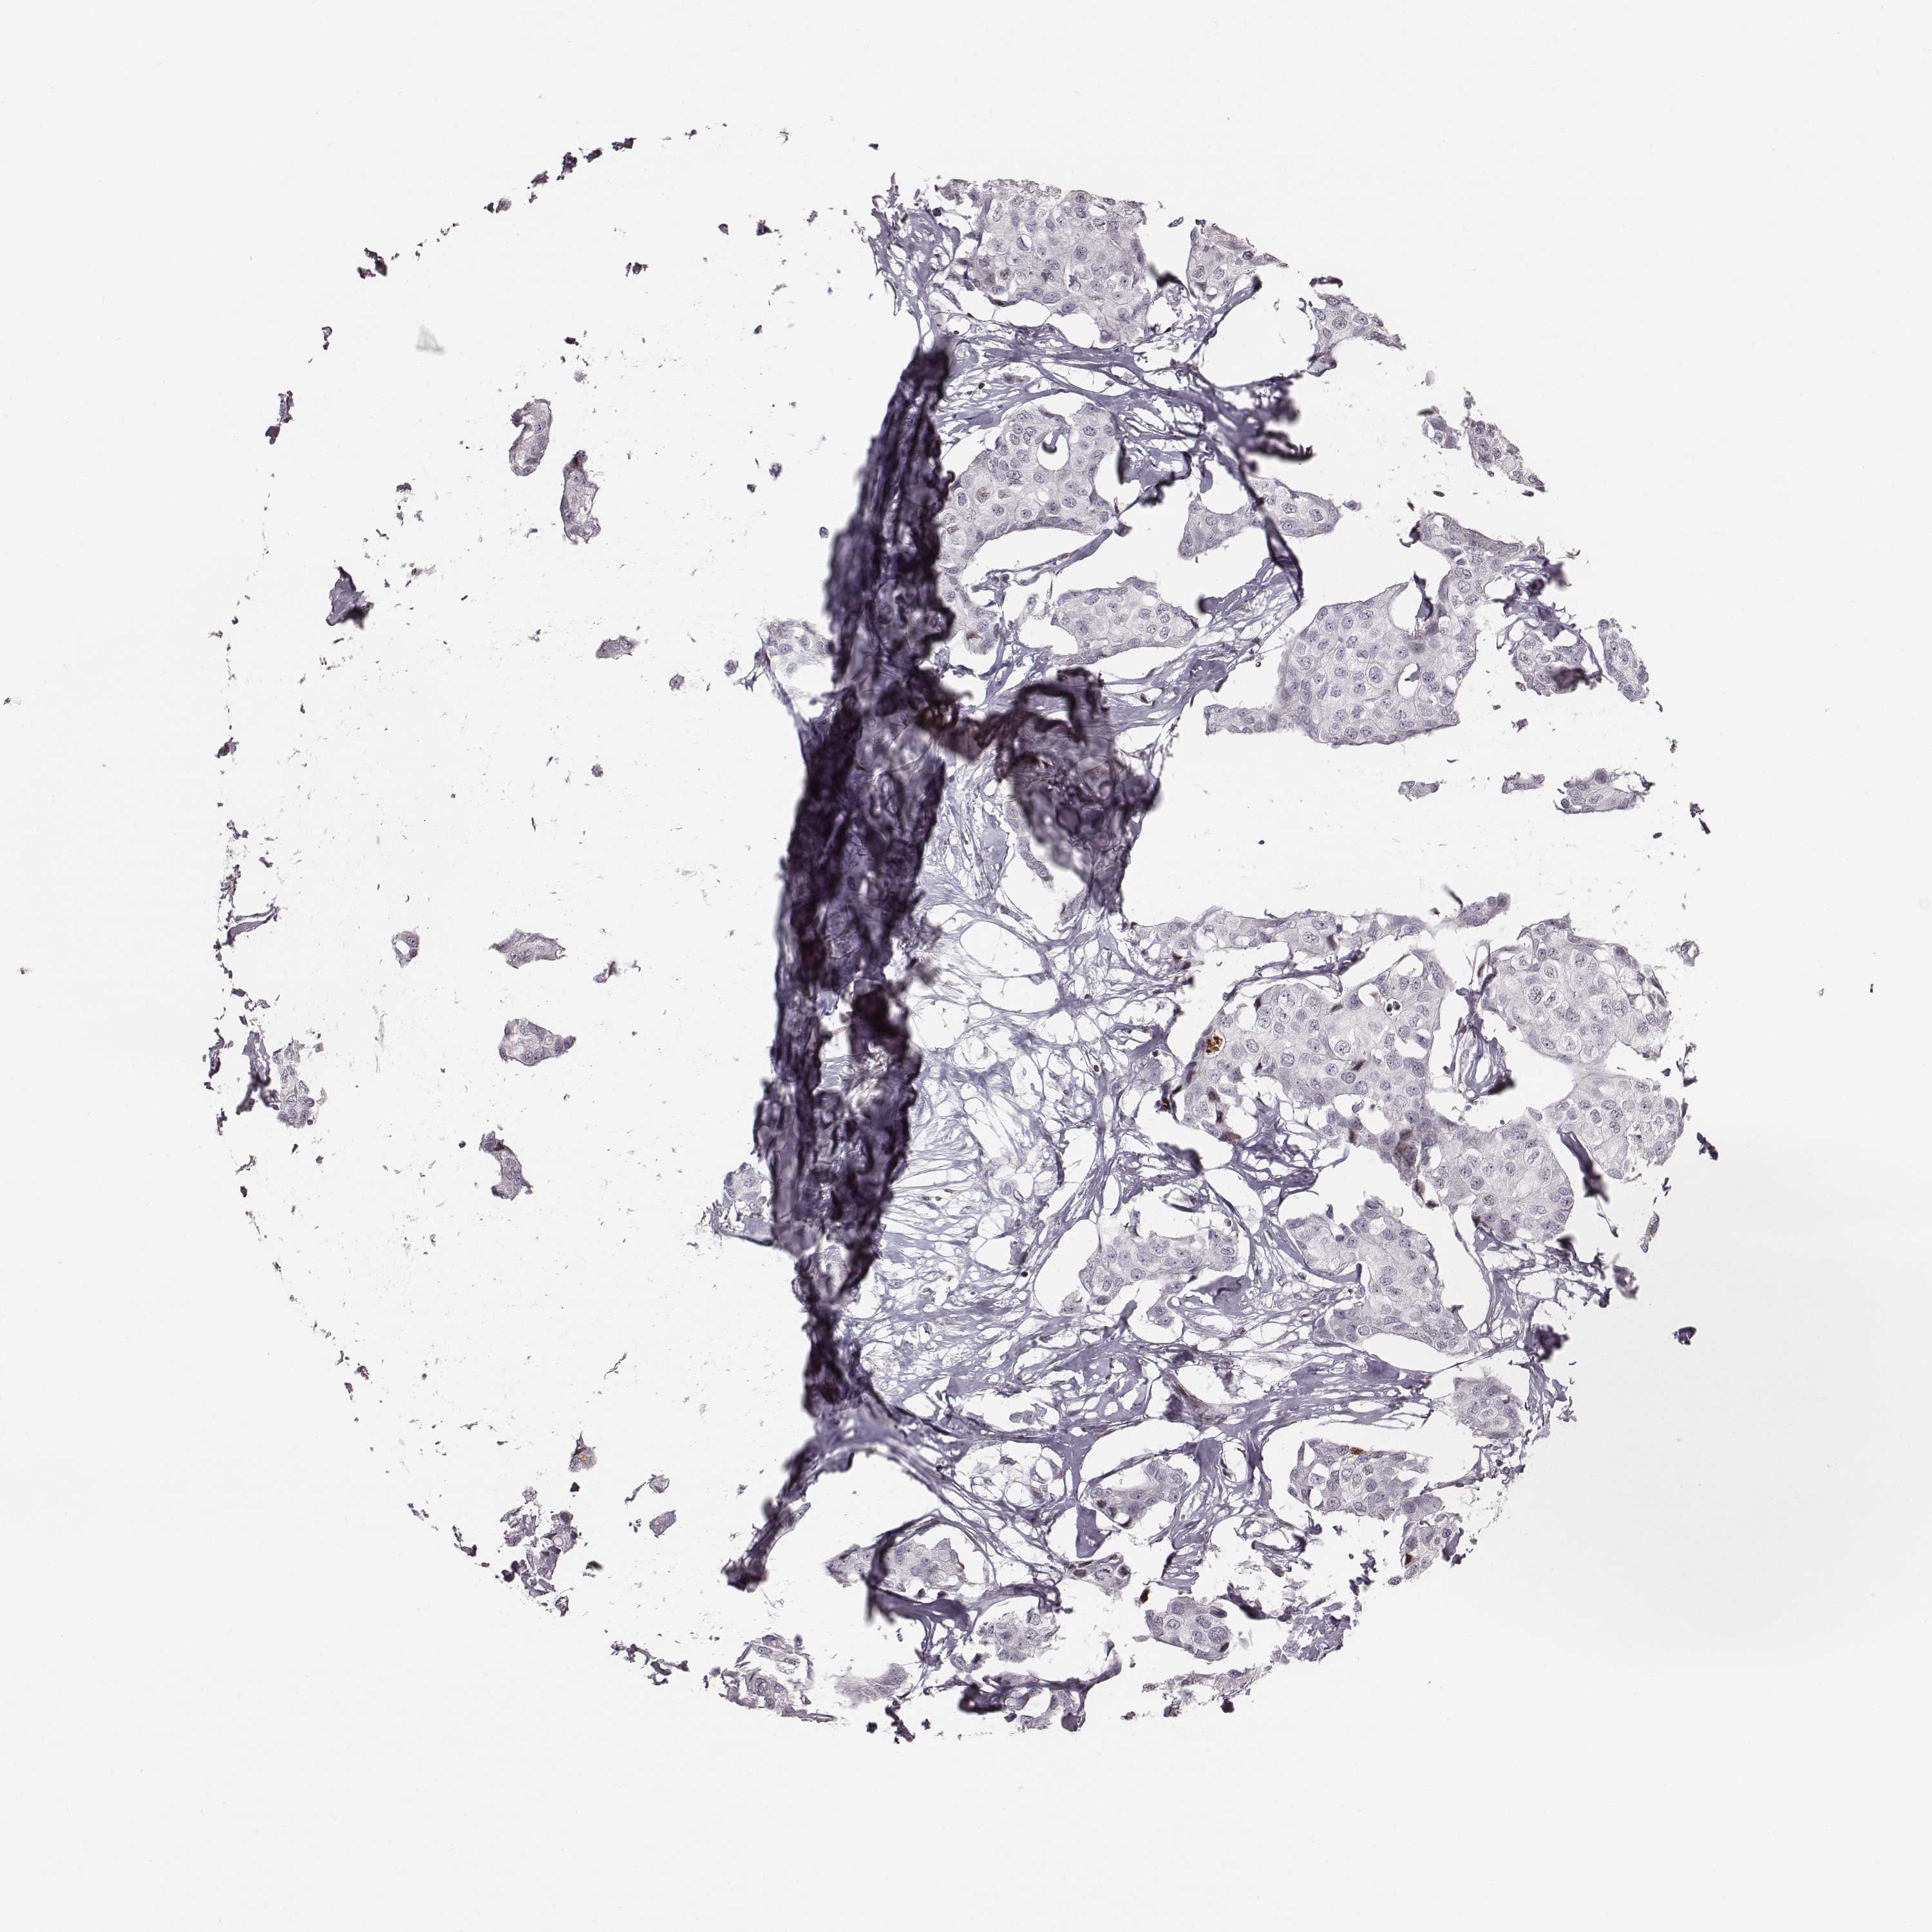

Breast cancer

Human cancer

CANCER BREAST CANCER Show tissue menu